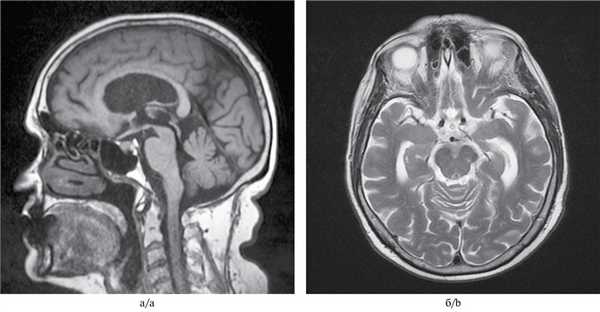

МРТ-исследование проведено на магнитно-резонансном томографе «Siemens» с напряженностью магнитного поля 1,5 Тл, с получением стандартных Т1- и Т2-взвешенных изображений (Т1-ВИ, Т2-ВИ) в фронтальной, аксиальной и сагиттальной плоскостях, с последующей оценкой визуальных изменений головного мозга (см. рисунок). Выявлены признаки атрофии среднего мозга с симптомами колибри в сагиттальной (см. рисунок, а) и Микки Мауса в аксиальной плоскостях (см. рисунок, б).

МРТ головного мозга 79-летней пациентки с ПНП.

а — Т1-взвешенное изображение, сагиттальная плоскость. Атрофия среднего мозга, сохранение объема моста и атрофия крыши среднего мозга. Симптом клюва колибри; б — Т2-взвешенное изображение на аксиальном срезе на уровне среднего мозга. Атрофия среднего мозга с формированием симптома Микки Мауса.